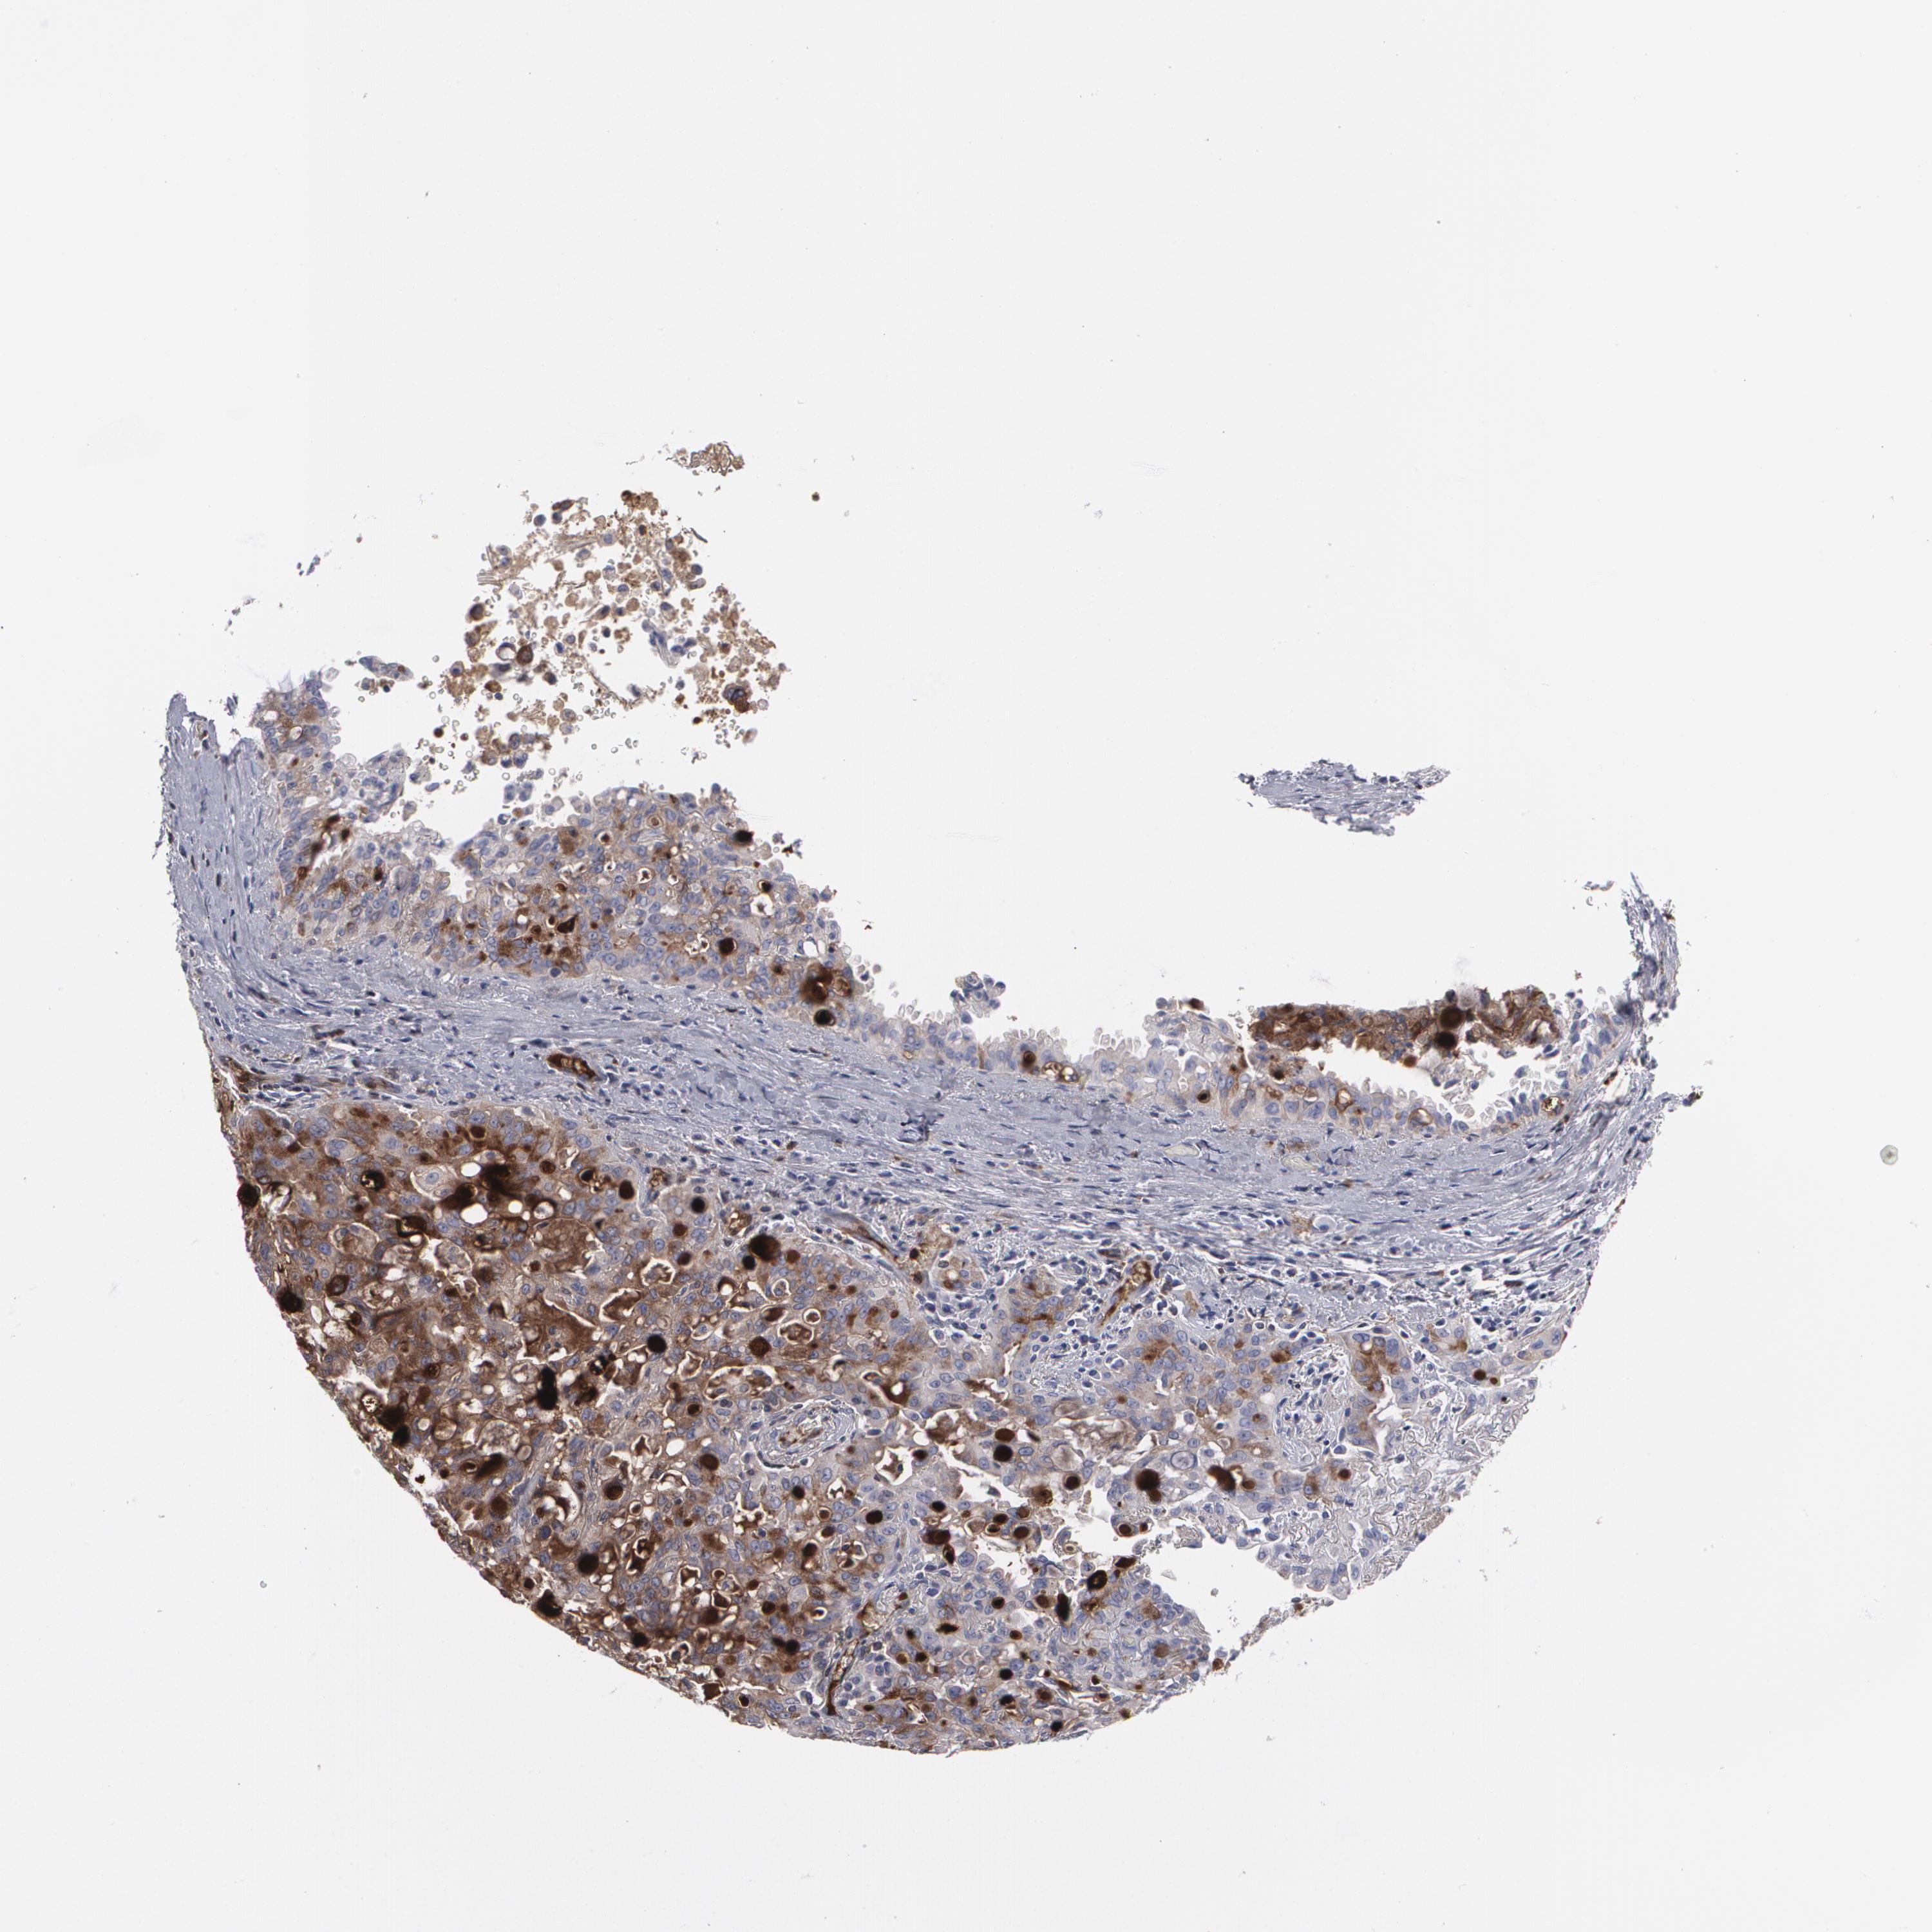

LUNG SQUAMOUS CELL CARCINOMA (TCGA) - Interactive survival scatter ploti

The Survival Scatter plot shows the clinical status (i.e. dead or alive) for all individuals in the patient cohort, based on the same data that underlies the corresponding Kaplan-Meier plots. Patients that are alive at last time for follow-up are shown in blue and patients who have died during the study are shown in red.

The x-axis shows the expression levels (FPKM) of the investigated gene in the tumor tissue at the time of diagnosis. The y-axis shows the follow-up time after diagnosis (years). Both axes are complimented with kernel density curves demonstrating the data density over the axes. The top density plot shows the expression levels (FPKM) distribution among dead (red) and alive patients (blue). The right density plot shows the data density of the survived years of dead patients with high and low expression levels respectively, stratified using the cutoff indicated by the vertical dashed line through the Survival Scatter plot. This cutoff is automatically defined based on the FPKM cutoff that minimizes the p-score. The cutoff can be changed by dragging the vertical line or by entering a cutoff value in the square labeled "Current cut-off".

Under the Survival Scatter plot the p-score landscape (black curve; left axis) is shown together with dead median separation (red curve; right axis). Dead median separation is the difference in median mRNA expression between patients who have died with high and low expression, respectively. It is calculated as follows: median FPKM expression of dead patients with high expression - median FPKM expression of dead patients with low expression. This is intended to aid the user in visually exploring custom cutoffs and the associated p-scores and dead median separation.

Individual patient data is displayed and can be filtered by clicking on one or more of the category buttons on the top of the page. Categories describing expression level and patient information include: high, low, alive, dead, female, male and tumor stages. The scale of the x-axis can be toggled between linear and log-scale by clicking on the "x log" button. Mouse-over function shows TCGA ID, patient information and mRNA expression (FPKM) for each patient.

& Survival analysisi

Kaplan-Meier plots summarize results from analysis of correlation between mRNA expression level and patient survival. Patients were divided based on level of expression into one of the two groups "low" (under cut off) or "high" (over cut off). X-axis shows time for survival (years) and y-axis shows the probability of survival, where 1.0 corresponds to 100 percent.

LRG1 is not prognostic in Lung Squamous Cell Carcinoma (TCGA)

: 7.43

Average pTPM 13.8

Number of samples 489